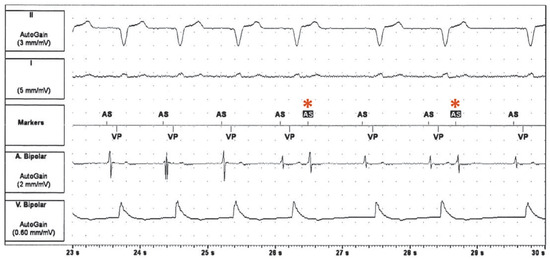

Recurrent Tachycardia During Pacemaker Interrogation

by Tobias Reichlin, Michael Kühne, Beat Schär and Christian Sticherling

Cardiovasc. Med. 2015, 18(6), 195; https://doi.org/10.4414/cvm.2015.00336 - 24 Jun 2015

Viewed by 71

Abstract

A 76-year-old man was seen in the pacemaker clinic for routine follow-up [...] Full article

Show Figures

Figure 1